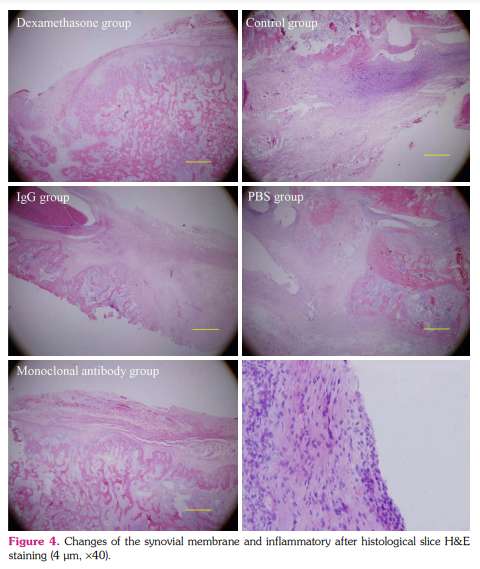

Pathological changes of rats treated with anti-RANKL monoclonal antibodies: As shown in Figure 4, joint organizations of different groups had synovial hyperplasia of fibrous tissue, cartilage and bone destruction in different degrees. The structural of synovial joints of rats in normal control group were complete, and displayed joint clearance, articular cartilage surface integrity and regular cell arrangement. Besides, there was obvious synovial tissue hyperplasia, inflammatory cells infiltration, fibrous tissue hyperplasia and pannus formation in CIA rats. After treatment with anti-RANKL monoclonal antibody, the above pathological changes improved to normal.